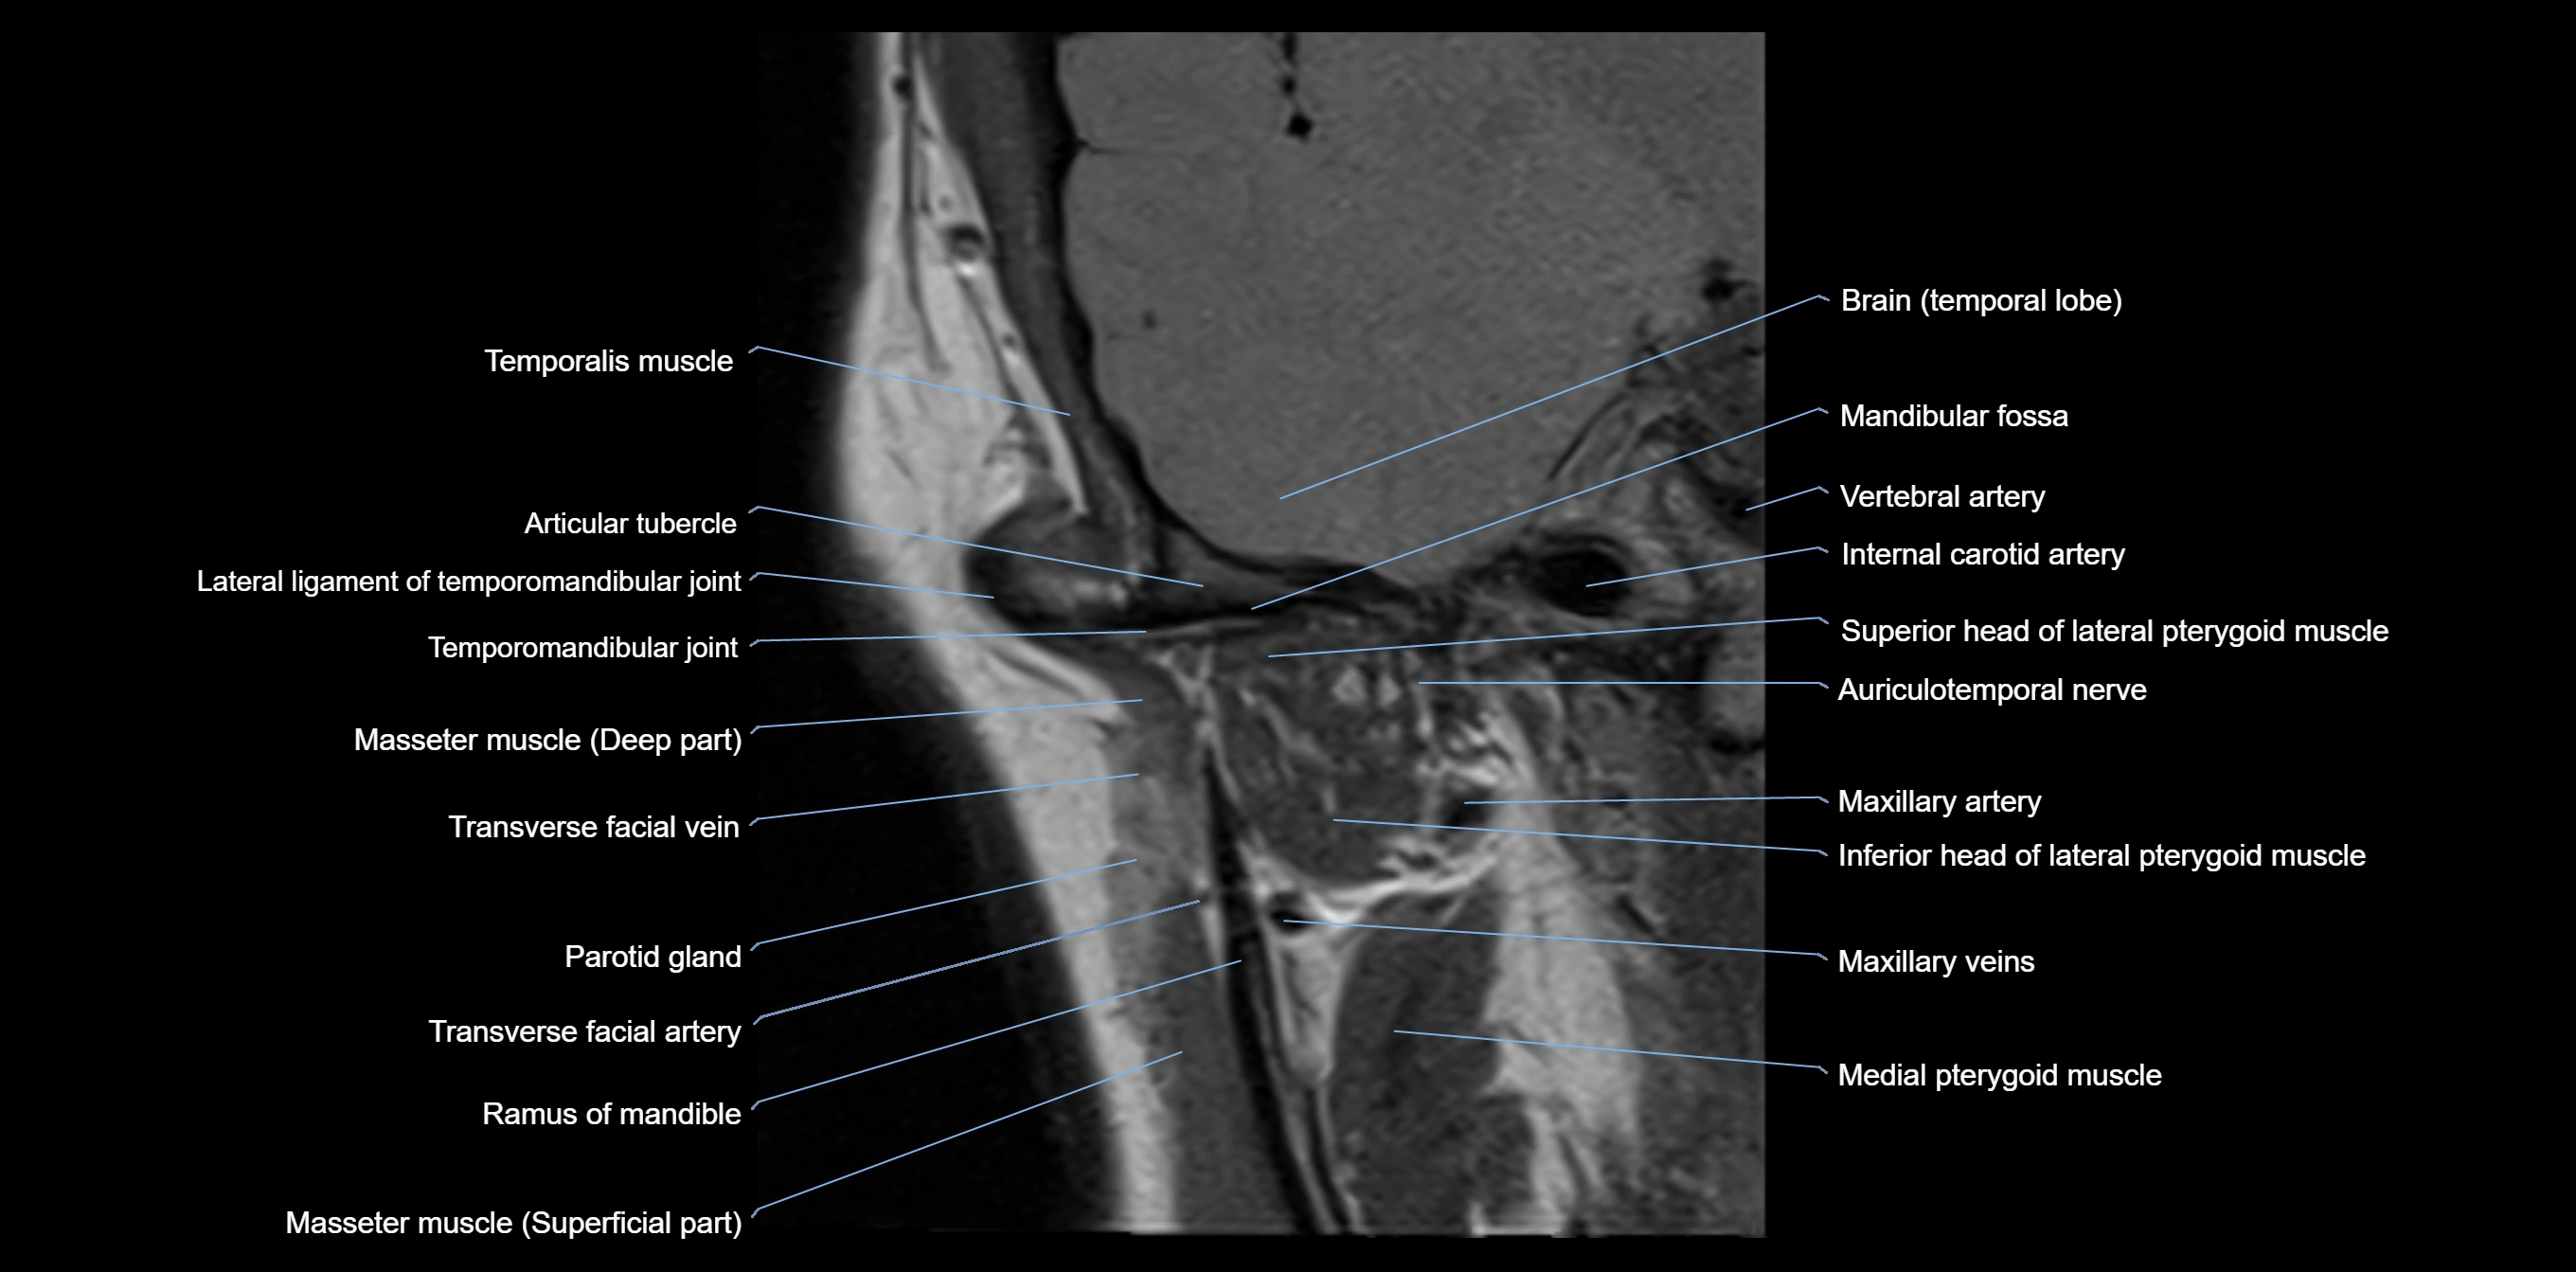

MRI appearance

T1-weighted images:

• Cortical bone: Low signal intensity

• Cancellous marrow: Intermediate to high signal depending on fatty content

• Teeth: Signal void structures

• Adjacent soft tissues: Normal gingiva and oral mucosa signal

T2-weighted images:

• Cortical bone and teeth: Low signal

• Marrow: Intermediate signal